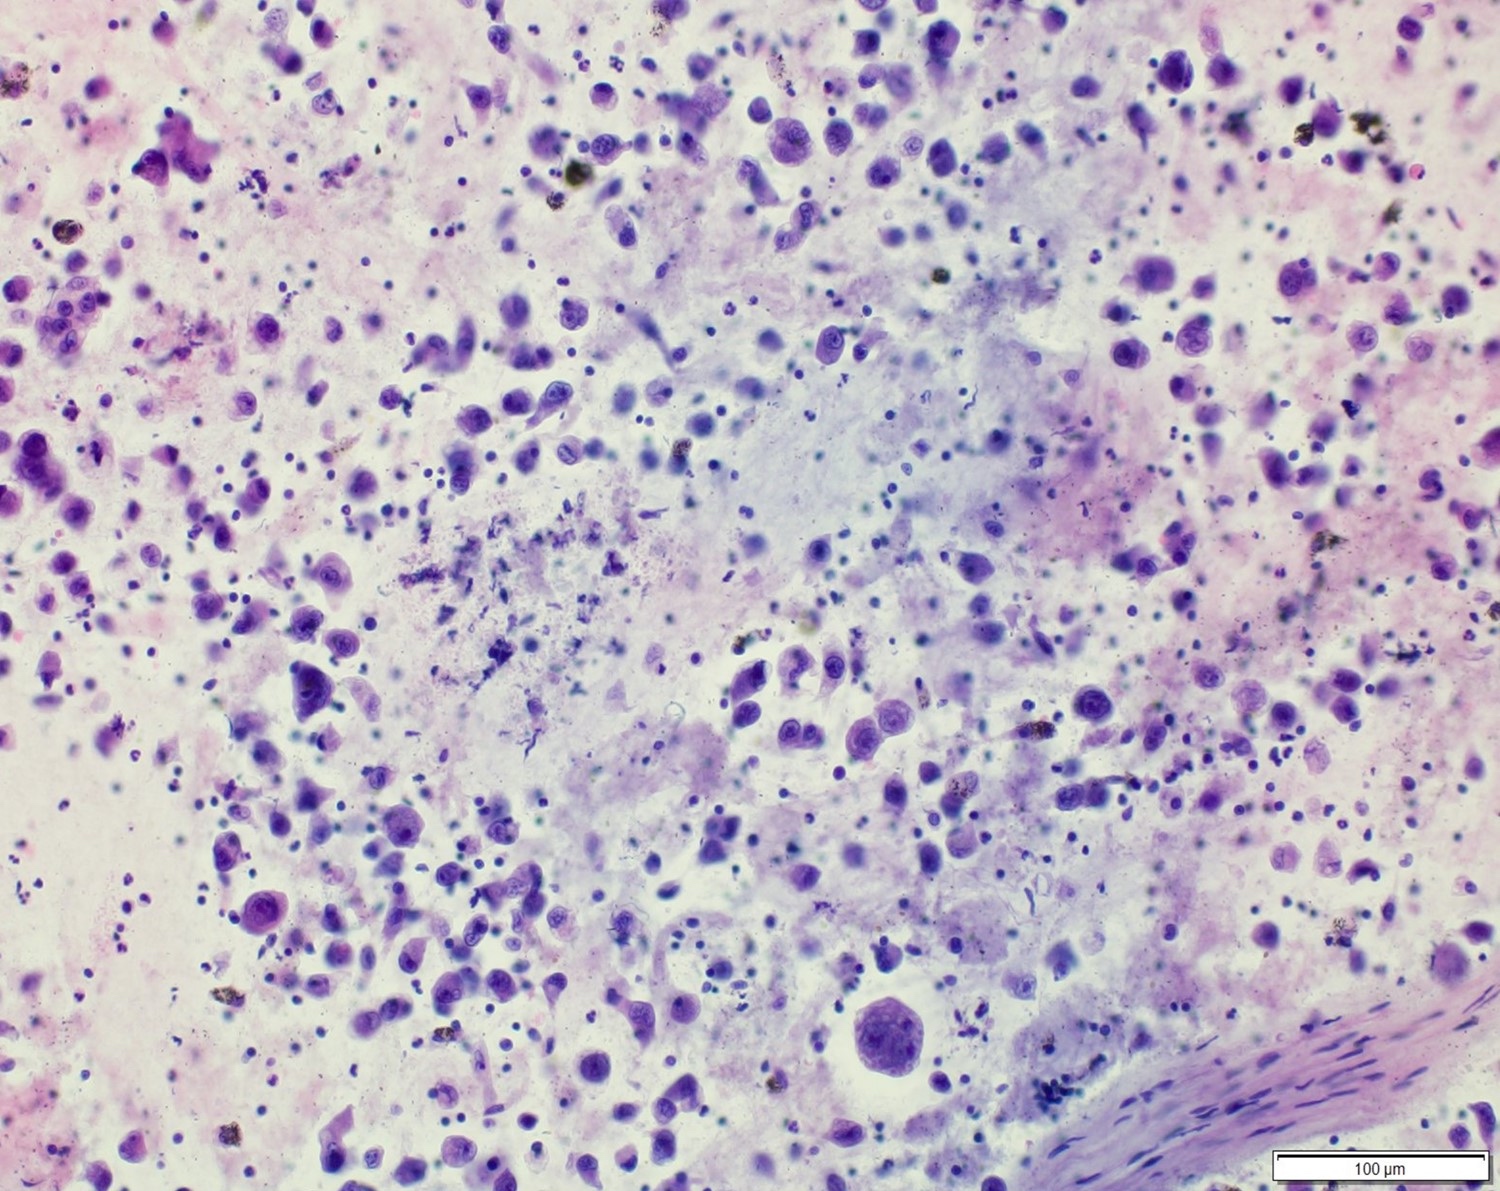

A 55 year old man presents with abdominal pain, weight loss and hepatomegaly. Laboratory studies reveal elevated liver enzymes but normal alpha fetoprotein levels. A liver core needle biopsy is performed. ERG immunohistochemistry is shown in the second image above. What is the most likely diagnosis?

E. Liver angiosarcoma. The histopathology shows nests and sheets of highly atypical neoplastic cells with hyperchromatic and pleomorphic nuclei, which are highlighted by ERG immunohistochemistry in the second image above. This makes liver angiosarcoma the most likely diagnosis.